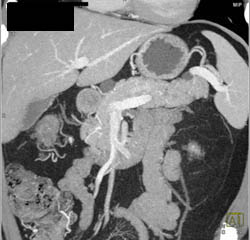

Multiple Intraductal Papillary Mucinous Neoplasms (IPMNs)